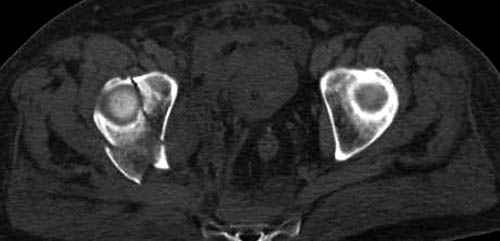

Судя по снимкам еще имеется перелом головки плеча, и чрезкостный отрыв вращательной манжеты. Для уточнения характера перелома не иешало бы сделать КТ. Если вести консервативно, то после сращения перелома будет ограничение движений в суставе не устраивающее больную. Я склоняюсь к оперативному лечению( накостный остеосинтез Т- Г образная пластина, лучше LCP для проксимальног плеча, обязательно подшить на место манжету).

Снимки на 1-е сутки после репозиции и на 8- сутки после репозиции.

Пожалуйста

С ув. Sergey A. Melashenko, г. Запорожье